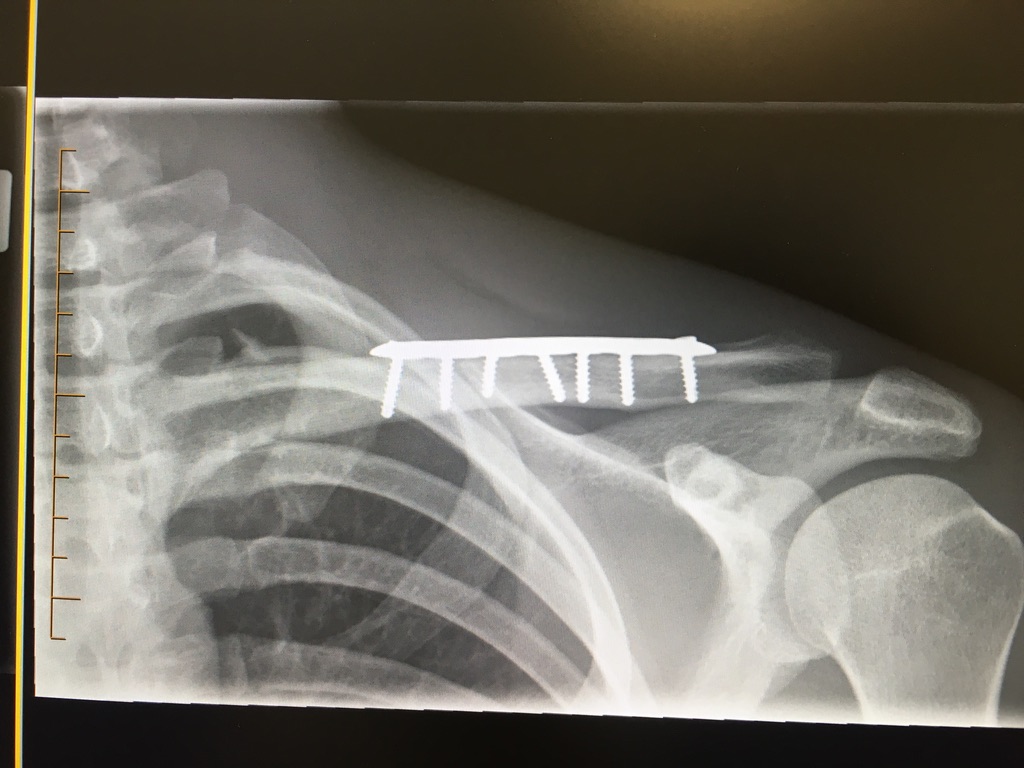

bones

I exhume them and build

your structure